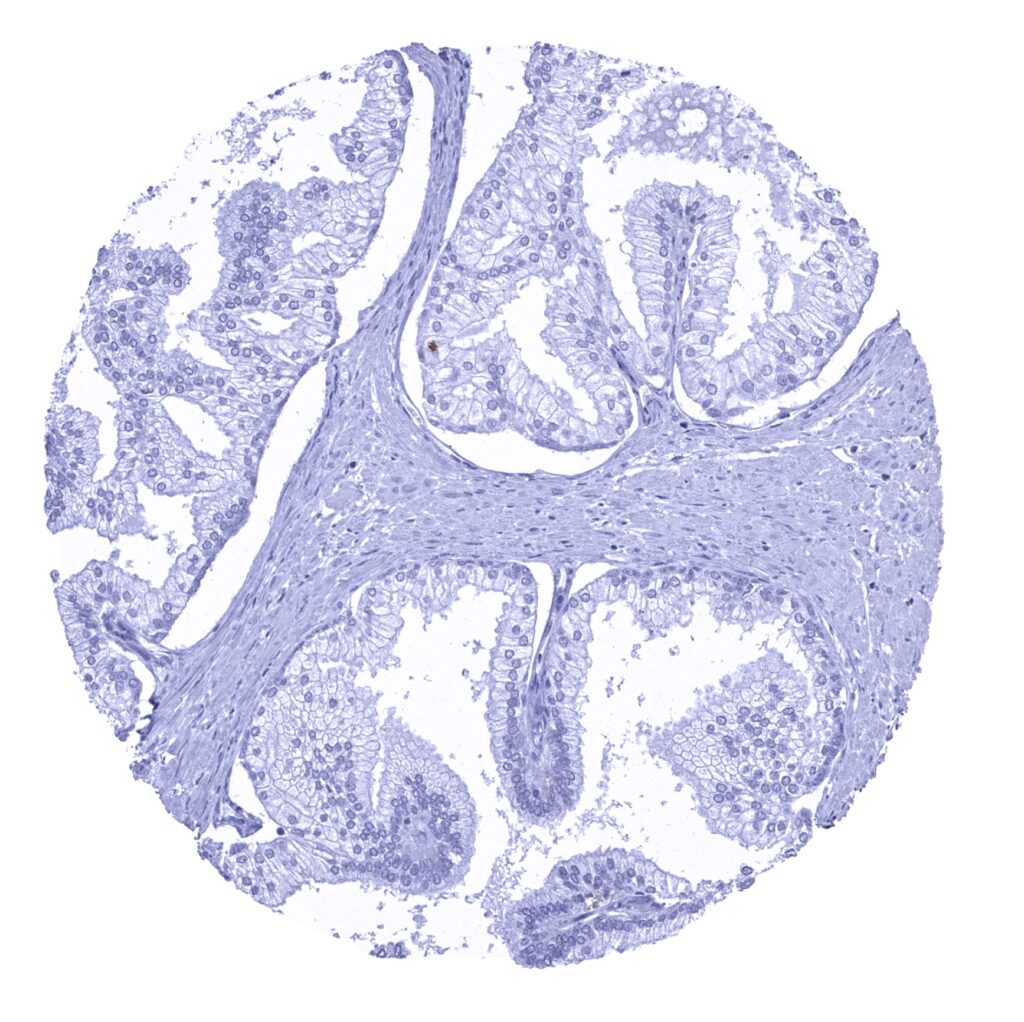

Appendix, mucosa